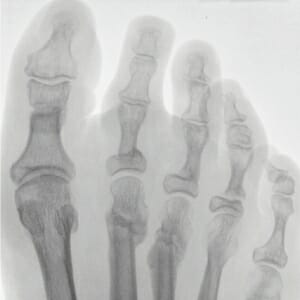

Abb. 2

6 Wochen nach minimalinvasiver Korrekturoperation mit Lösung der Zehen-Mittelgelenke Z 2, 3, 4 und percutaner Lösung der Zehengrundgelenke mit Verlängerung der Strecksehnen und Verkürzungsosteotomien der Mittelfußknochen 2 und 3.